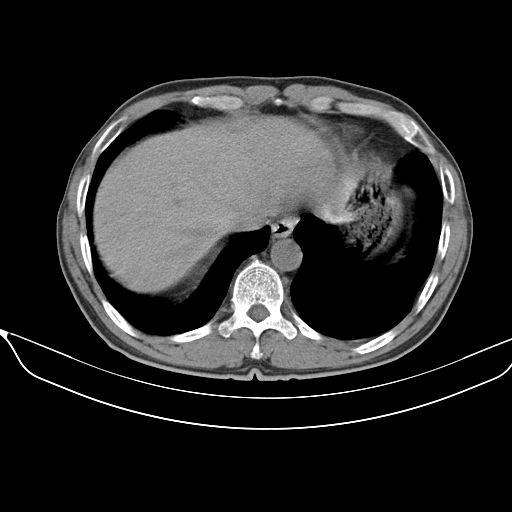

以下是引用心路寻觅在2010-3-1 10:23:00的发言:[br]1、考虑左肺上叶周围型肺癌[br]2、右上肺陈旧性病灶。[br][br][本贴已被 心路寻觅 于 2010-3-1 10:40:18 修改过]

以下是引用shuiyuan在2010-3-1 10:45:00的发言:[br]考虑左肺上叶中心型肺癌伴阻塞型炎症,邻近胸膜受侵。